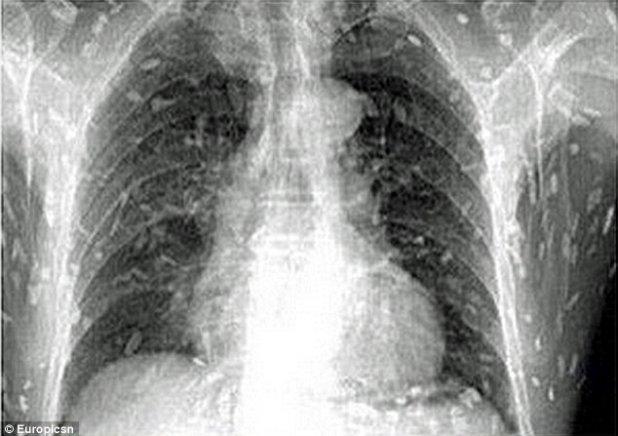

A ajuns la urgenţe cu dureri de stomac şi o senzaţie de mâncărime pe întreg corpul. Ce au descoperit medicii în corpul său i-a lăsat fără cuvinte

Foto: Europicsn